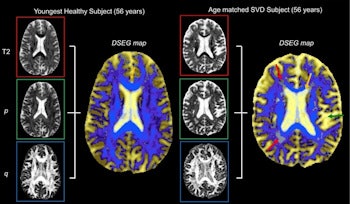

Diffusion tensor image segmentation color maps of the brain from healthy subject and age-matched SVD subject. By overlaying T2, p and q images, brain sensitive alterations in brain microstructure are visible. Red arrows indicate white matter hypersensitivities; orange arrow shows corpus callosum; green arrow shows the greater volume of cerebrospinal fluid space. © 2017 The Authors (CC BY-NC-ND 4.0).

The DSEG technique enables imaging of gray matter, white matter, cerebrospinal fluid, and white matter hypersensitivities, which when combined to create a DSEG Θ angular score can quantify brain damage effectively. The authors note a limitation of this study is the lack of consideration for the spatial location of SVD-related pathology.

Common imaging techniques for diagnosing and monitoring SVD only use a single marker, which does not always correlate strongly with disease progression and cognitive decline. The DSEG technique acquires scores by comparing SVD patients' brain scans with those of age-matched healthy controls. This process accurately depicts microstructure changes within the brain.